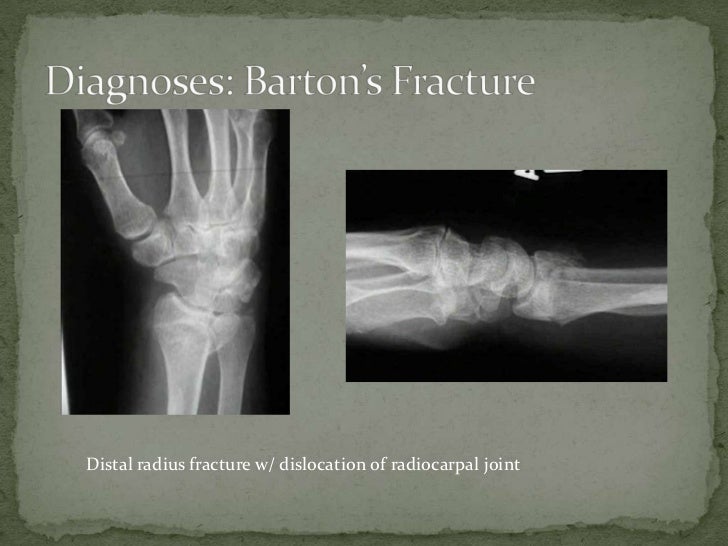

Barton's fracture hand (or distal joint) articulated to distal

Distal End Radius Fractures Colles, Smiths & Bartons Barton Fracture X Ray It is also sometimes termed the dorsal type barton fracture to distinguish it. A barton fracture is a painful, dislocated wrist fracture that causes swelling and numb or tingling fingertips. Barton fractures are fractures of the distal radius. A barton fracture can be described as volar (more common) or dorsal (less common), depending on whether the volar or dorsal rim. Barton Fracture X Ray.